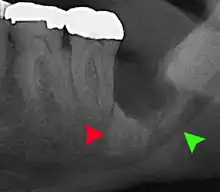

Impacted wisdom tooth with a backward tilt (distoangular impaction) and chronic infection to back of crown (green arrow)

Impacted 2nd molar (red arrow) with developing wisdom tooth (green arrow)

There is no standard to screen for wisdom teeth. It has been suggested, absent evidence to support routinely retaining or removing wisdom teeth, that evaluation with panoramic radiograph, starting between the ages of 16 and 25 be completed every 3 years. Once there is the possibility of the teeth developing disease, then a discussion about the operative risks versus long-term risk of retention with an oral and maxillofacial surgeon or other clinician trained to evaluate wisdom teeth is recommended. These recommendations are based on expert opinion level evidence.[19] Screening at a younger age may be required if the second molars (the "12-year molars") fail to erupt as ectopic positioning of the wisdom teeth can prevent their eruption. Radiographs can be avoided if the majority of the tooth is visible in the mouth.